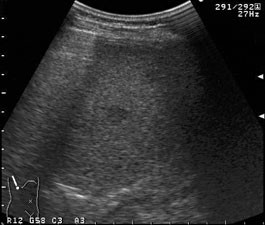

C型肝炎患者の経過観察中に出現した低エコー結節。10数mm大の結節が2箇所見られる。  |